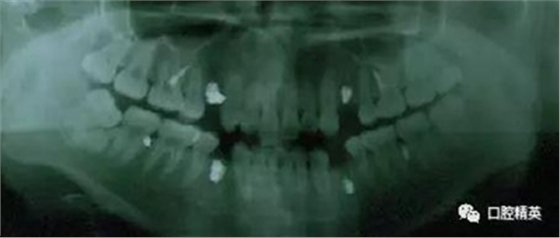

再次,植入微型種植體,在附著牙齦處不需要粘骨膜翻瓣,在牙槽黏膜處則需要切開黏膜以避免植入時(shí)軟組織被卷入,植入部位通常在膜齦結(jié)合部位或偏根方2~3mm,植入角度與骨面垂直并傾斜15~20度,即向根尖方向植入,術(shù)后拍根尖片以確認(rèn)與牙根的關(guān)系。術(shù)后口服抗生素預(yù)防感染并進(jìn)行口腔衛(wèi)生宣教。

上頜種植釘?shù)闹睆?.6,長度11mm;下頜直徑2.0,長度9mm

1、上頜種植釘常見位置在5,6之間;下頜種植釘常見位置在6,7之間。

2、助攻型種植釘,上頜與頜骨成30-40°角,下頜與頜骨成10-20°角(目的:1、降低損傷牙根及牙周膜的機(jī)率;2、使種植釘盡量植入骨皮質(zhì)內(nèi),降低松動機(jī)率);自攻型種植釘與頜骨垂直;個(gè)人習(xí)慣:自攻型種植釘上下頜均與頜骨成30-40°角。